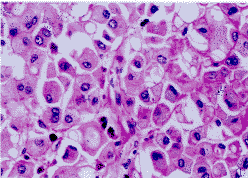

光鏡下表現為高度惡性肉瘤圖像,瘤細胞呈瀰漫性或不規則巢狀排列,特徵性表現是含豐富嗜酸性胞漿的大多角形細胞,泡狀核,核仁明顯,呈“貓頭鷹眼樣”。部分核偏位,大部分胞漿內見透明、淡嗜伊紅的球形包涵體,PAS陽性。電鏡下見包涵體由呈漩渦狀或同心圓狀排列的中間絲或微絲組成。

瘤細胞胞漿及包涵體vimentin,cytokeratin瀰漫陽性。Cytokeratin各型中,主要可見CK8和CK18陽性。大部分細胞胞漿CD99、NSE、Leu7等陽性。